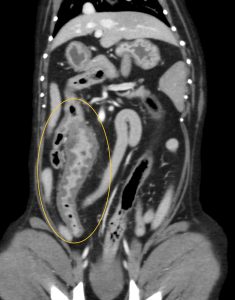

超音波検査を行ったところ、回腸から盲腸、結腸にかけて腸の肥厚と構造の破壊が認められました。腫瘍の可能性も考慮されたため、CT検査と手術(回盲部切除)を行いました。

病理組織学的検査では、リンパ液漏出に伴う肉芽腫性腸炎と診断されました。今後は、食事管理、内科治療が継続的に必要で、再発にも注意が必要です。